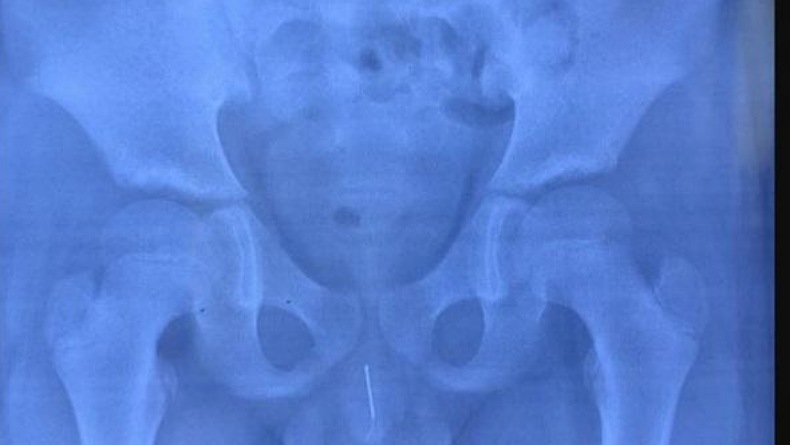

SHANGHAI, iNews.id - Kondisi tak biasa menimpa Xiao Huang (11) saat dokter memeriksa foto X-Ray. Dokter di China terkejut bukan main mendapati jarum akupuntur 8 cm ada di uretra penis anak itu.

Dokter pun segera melakukan pemeriksaan dengan sinar X-Ray. Mereka menemukan jarum yang terjebak di sana diduga sekitar 12 jam terakhir.